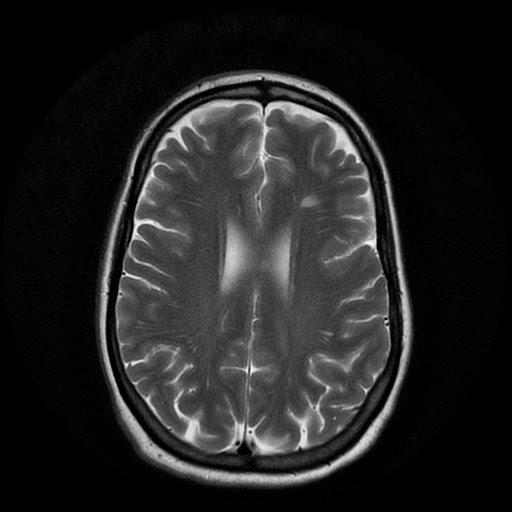

From radiologycases.blogspot.com

Radiology Cases MS presenting with severe headache Does Ms Start With Headaches A person with multiple sclerosis (ms) may experience various types of headaches. Some people with ms are more likely to experience certain types of. What does a headache with ms feel like? Most headaches , those associated with ms included, fall into one of three categories: In fact, research suggests ms may have a prodromal (very early) phase. This phase. Does Ms Start With Headaches.